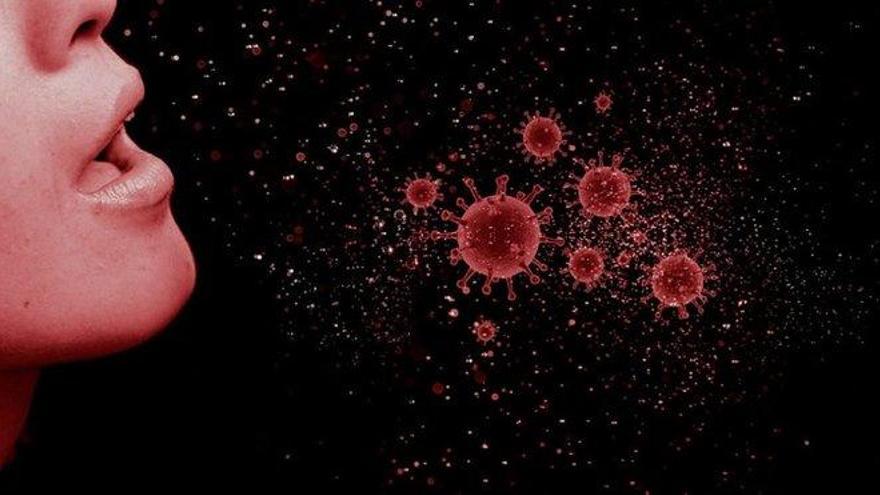

Después de meses de pandemia mundial los científicos continúan descubriendo nuevos datos y características del coronavirus Covid-19 que esta azotando a una multitud de países y ya casi ha dejado un millón de muertos en todo el mundo (cifras oficiales). Ahora el Centro para el Control y Prevención de Enfermedades (CDC) estadounidense informa de que la mayor vía de propagación del virus es el aire.

Esto es un dato muy importante que se llevaba estudiando desde el inicio de la pandemia ¿por donde se transmite el virus?, al comienzo de la misma la perspectiva de que fue un contagio vía aérea no era demasiado fuerte, pero ahora después de meses se ha confirmado. Esto significa que la OMS deberá cambiar sus propuestas para combatir la pandemia. Según la CDC las gotitas de saliva no se puede inhalar al considerarlas "proyectiles".